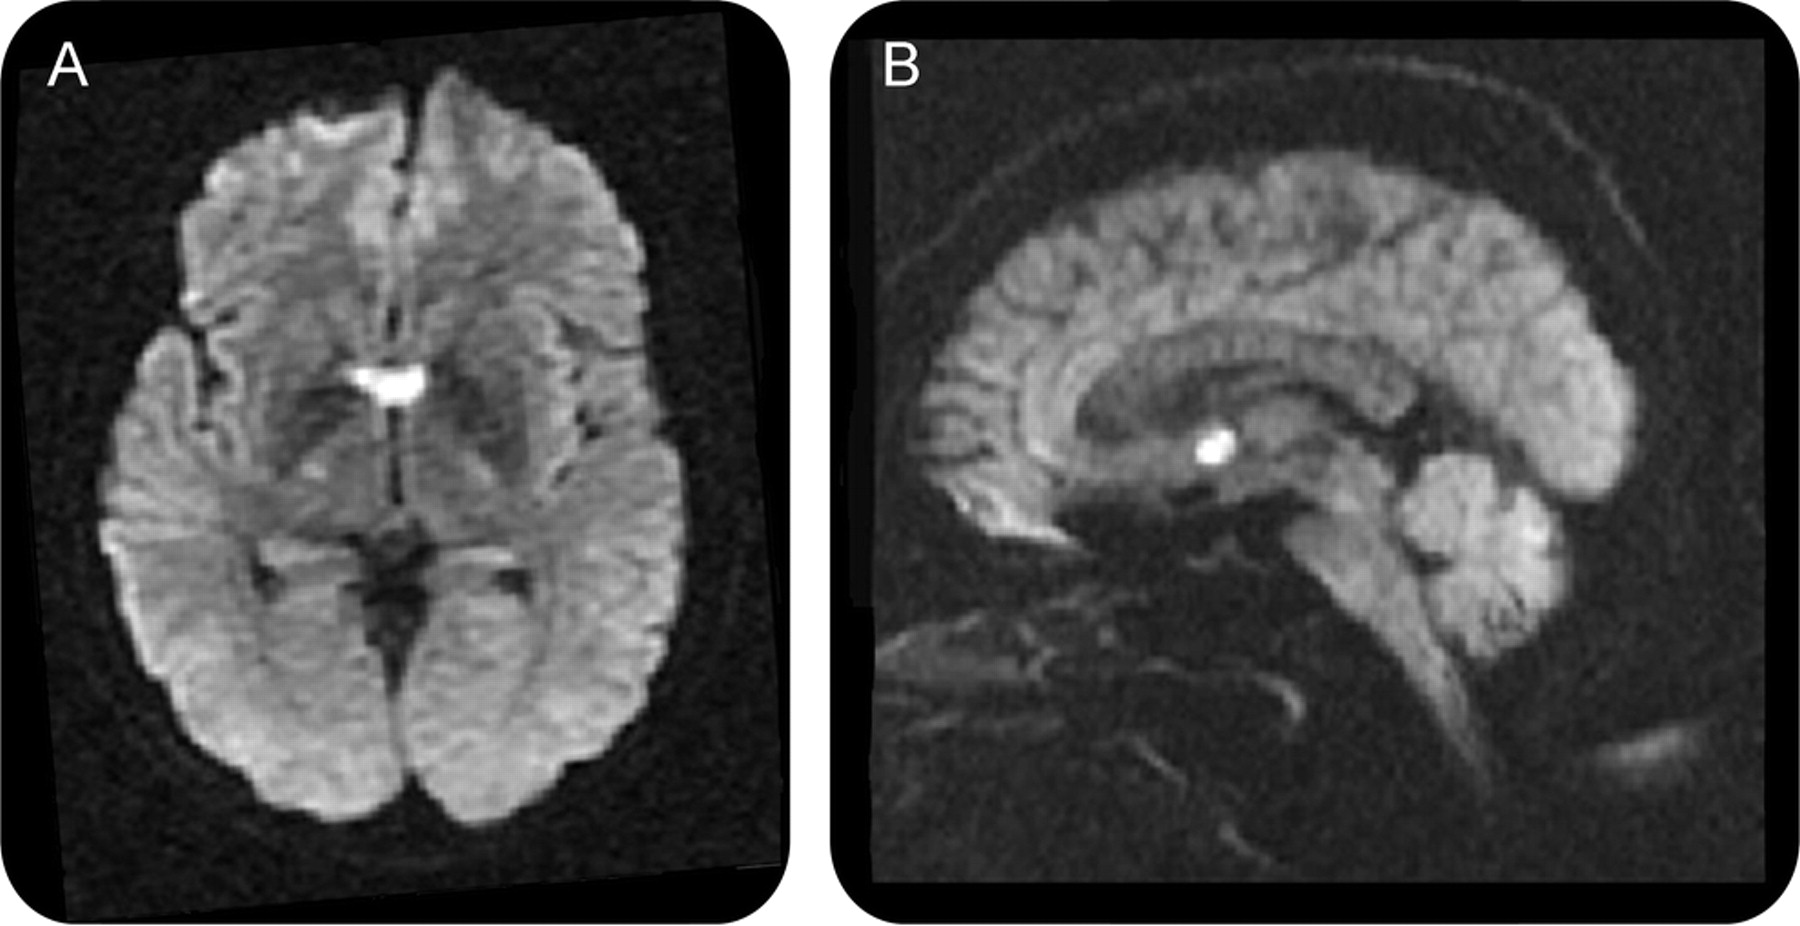

教学神经图片由于穹窿梗死:遗忘

一个53岁的右撇子老师发达急性混乱和短期记忆困难,包括重要的逆行,顺行性遗忘。智慧完好无损。她重复短语说最近没有召回,问不恰当的问题。

细微精神状态检查是正常的,除了不能回忆起任何3对象后5分钟。她没有其他神经系统异常。CT血管造影技术和超声心动图显示没有血栓栓塞源。失忆坚持2个月后。